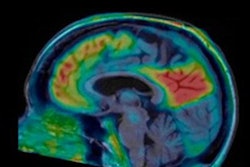

PET imaging could be a useful tool for diagnosis and treatment of idiopathic normal pressure hydrocephalus, a form of dementia that can be treated surgically, according to a literature review published September 7 in the International Journal of Molecular Sciences.

But these techniques aren't completely successful, according to the authors. Since PET imaging is regularly used to evaluate patients with neurodegenerative diseases, Mattoli's team sought to explore its role for diagnosing idiopathic normal pressure hydrocephalus through a literature review that included 35 papers that described results from 674 patients.